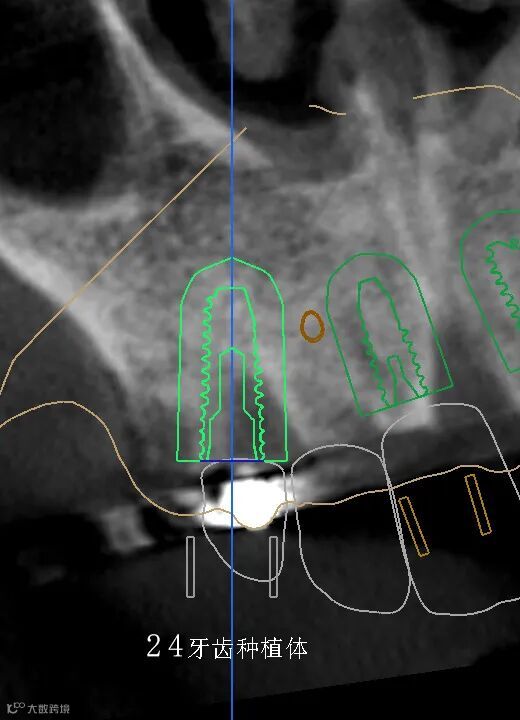

数字化种植手术规划与导板设计

临床种植手术过程